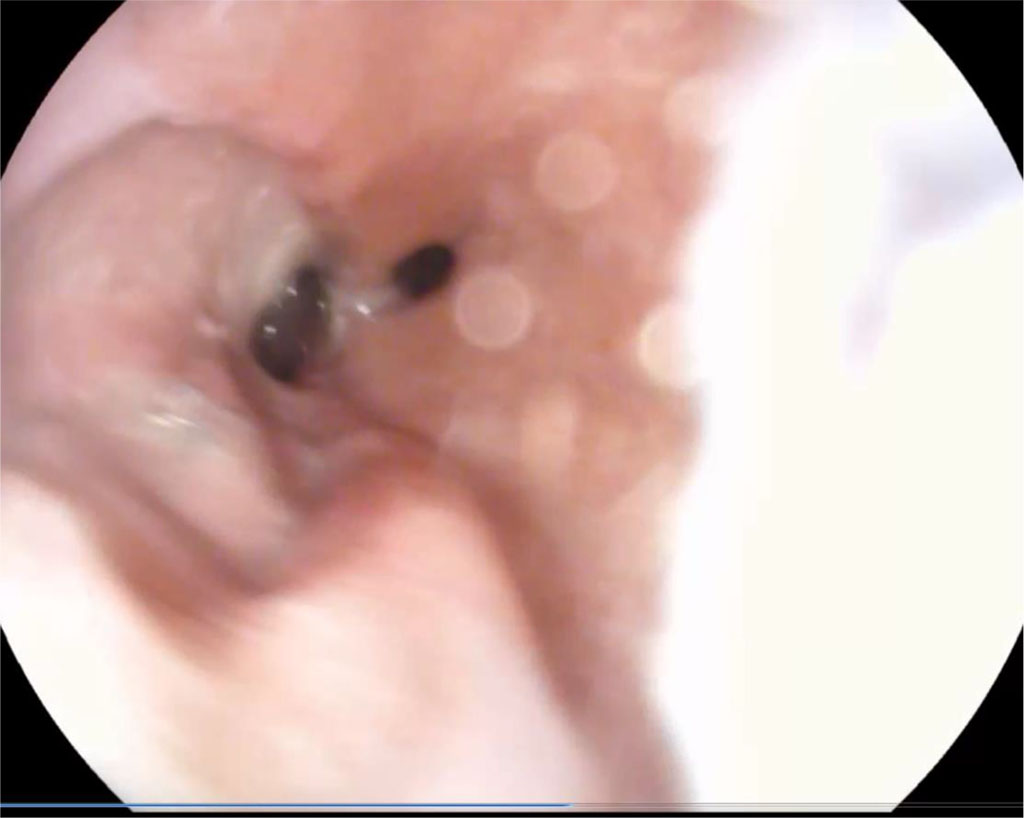

After 1.5 months, the fistula was almost completely closed with granulations. Fig. 3.

Figure 3. 1.5 months after surgery (explanations in the text)